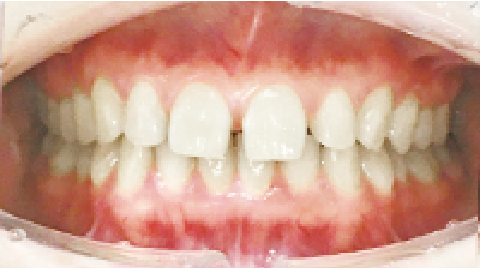

症例 : 9歳 男性

Before

After

主訴

反対咬合(受け口)

治療方法

プレオルソ+インビザファースト

総額治療費

660,000円(税込)

治療期間

6ヶ月

治療のリスク・副作用

下顎の後退中に顎に痛みを感じることがあります。

改善ポイント

上顎の拡大のためインビザラインファーストを行いつつ、上下関係を改善させるためにプレオルソを就寝時に着用し、下顎の後退を期待しました。